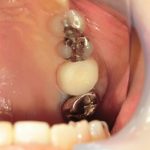

ジルコニアモノコックのクラウンで修復